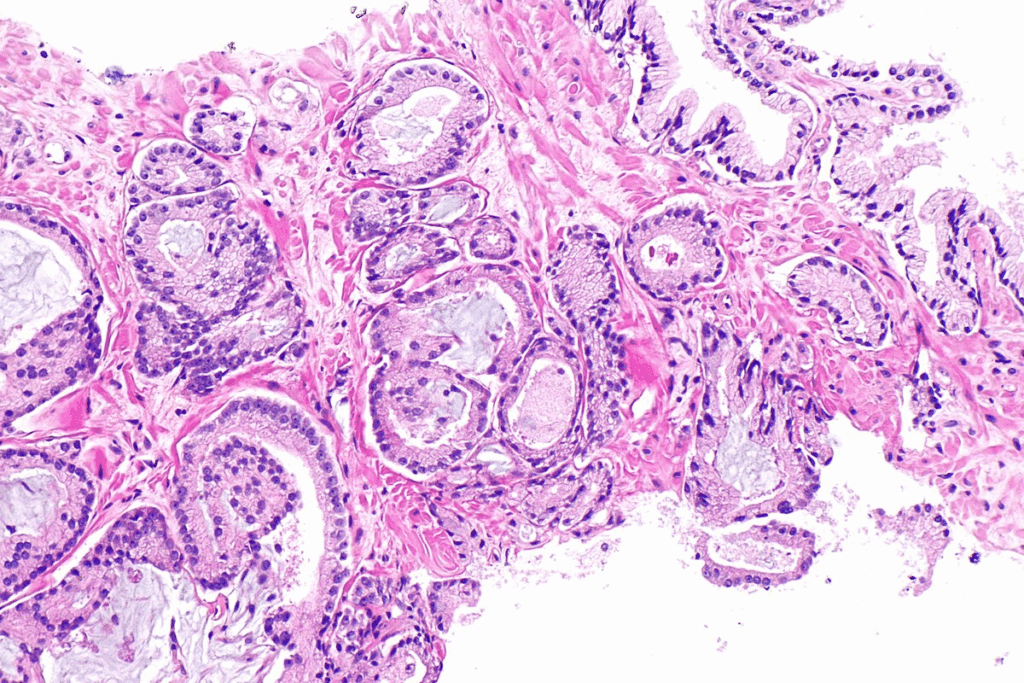

CIS bladder cancer, or carcinoma in situ, has high-grade malignant cells with severe changes. It looks flat and doesn’t form papillae like other cancers. This makes it hard to spot during regular cystoscopy.

Carcinoma in situ (CIS) bladder cancer is a high-grade, flat urothelial lesion. It’s different from other bladder cancers. Knowing this helps us understand CIS better.

CIS bladder cancer has high-grade malignant cells. These cells are in the urothelium but don’t invade the bladder wall. They have big nuclei and prominent nucleoli, showing they are high-grade.

CIS doesn’t form papillary structures like some bladder cancers do. Its flat appearance is a key diagnostic feature. This makes CIS different from low-grade papillary urothelial carcinomas.

Because CIS is flat, it’s hard to spot with cystoscopy alone. A detailed diagnosis is needed to find CIS.

It’s important to know the differences between CIS and other bladder cancers. The high-grade and flat nature of CIS highlights the need for quick and effective treatment. This helps prevent it from becoming invasive.